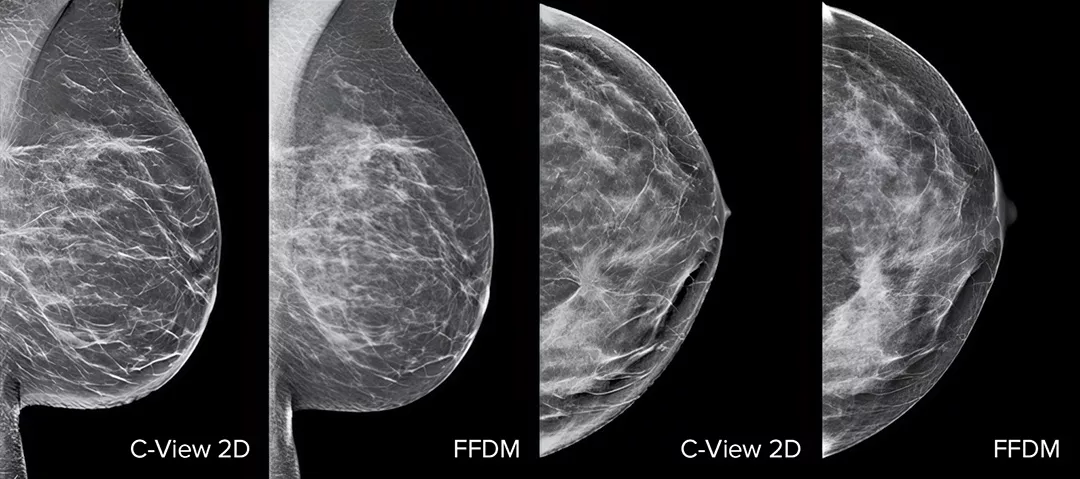

Les distorsions architecturales, les masses et les microcalcifications sont plus visibles sur une image 2D C-View que sur une image 2D classique ou une coupe de tomosynthèse.4,6-9

La preuve est dans le détail

Les images 2D C-View sont cliniquement prouvées3,5 et approuvées par la FDA pour remplacer les images 2D dans le cadre d’un examen de dépistage par tomosynthèse. Les images facilitent également la navigation lors de l’examen des coupes de tomosynthèse. Selon des études publiées, la mammographie 3D à faible dose détecte les cancers invasifs plus tôt, par rapport à la 2D seule, tout en réduisant les taux de rappels de faux-positifs.4,5,7

Images d’une radiographie du sein